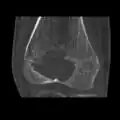

Chondoblastoma of thigh bone near knee (CT scan, non-contrast)

A variety of imaging studies can be used to diagnose chondroblastoma, with radiographs being the most common.[10][8] Laboratory studies are not considered useful.[14] Classical chondroblastoma (appearing on long bones) appears as a well-defined eccentric oval or round lytic lesion that usually involves the adjacent bone cortex without periosteal reaction.[10][13] A sclerotic margin can be seen in some cases.[10][13] For long bone chondroblastomas the tumor is typically contained to the epiphysis or apophysis but may extend through the epiphyseal plate.[10][13] Chondroblastomas are usually located in the medullary portion of bones and can, in some cases, include the metaphysis.[10][13] However, true metaphyseal chondroblastomas are rare and are typically the result of an extension from a neighboring epiphyseal legion.[10][13] Most lesions are less than 4 cm.[10] A mottled appearance on the radiograph is not atypical and indicates areas of calcification which is commonly associated with skeletally immature patients.[10] Additionally, one-third of all cases involve aneurysmal bone cysts which are thought to be the result of stress, trauma or hemorrhage.[10] In cases involving older patients or flat bones, typical radiographic presentation is not as common and may mimic aggressive processes.[10][13]

Other imaging techniques involve computed tomography (CT), magnetic resonance imaging (MRI), and bone scans, which may be helpful in determining the anatomical boundaries, associated edema, or biological activity of the chondroblastoma, respectively.[8][10] MRI studies may show extensive oedema around the lesion and show variable T2 signal intensity.[15]